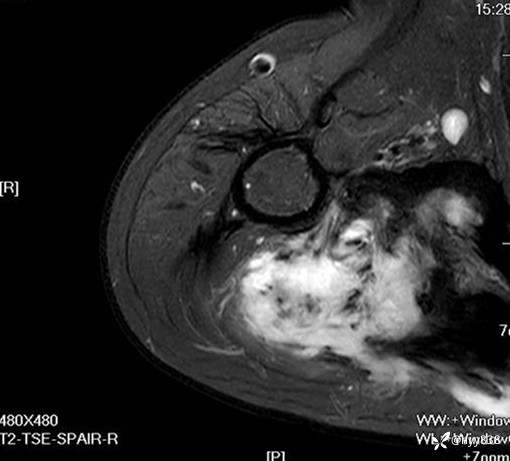

MRI AXI T1WI+T2WIfs

AXI T1WI+T2WIfs